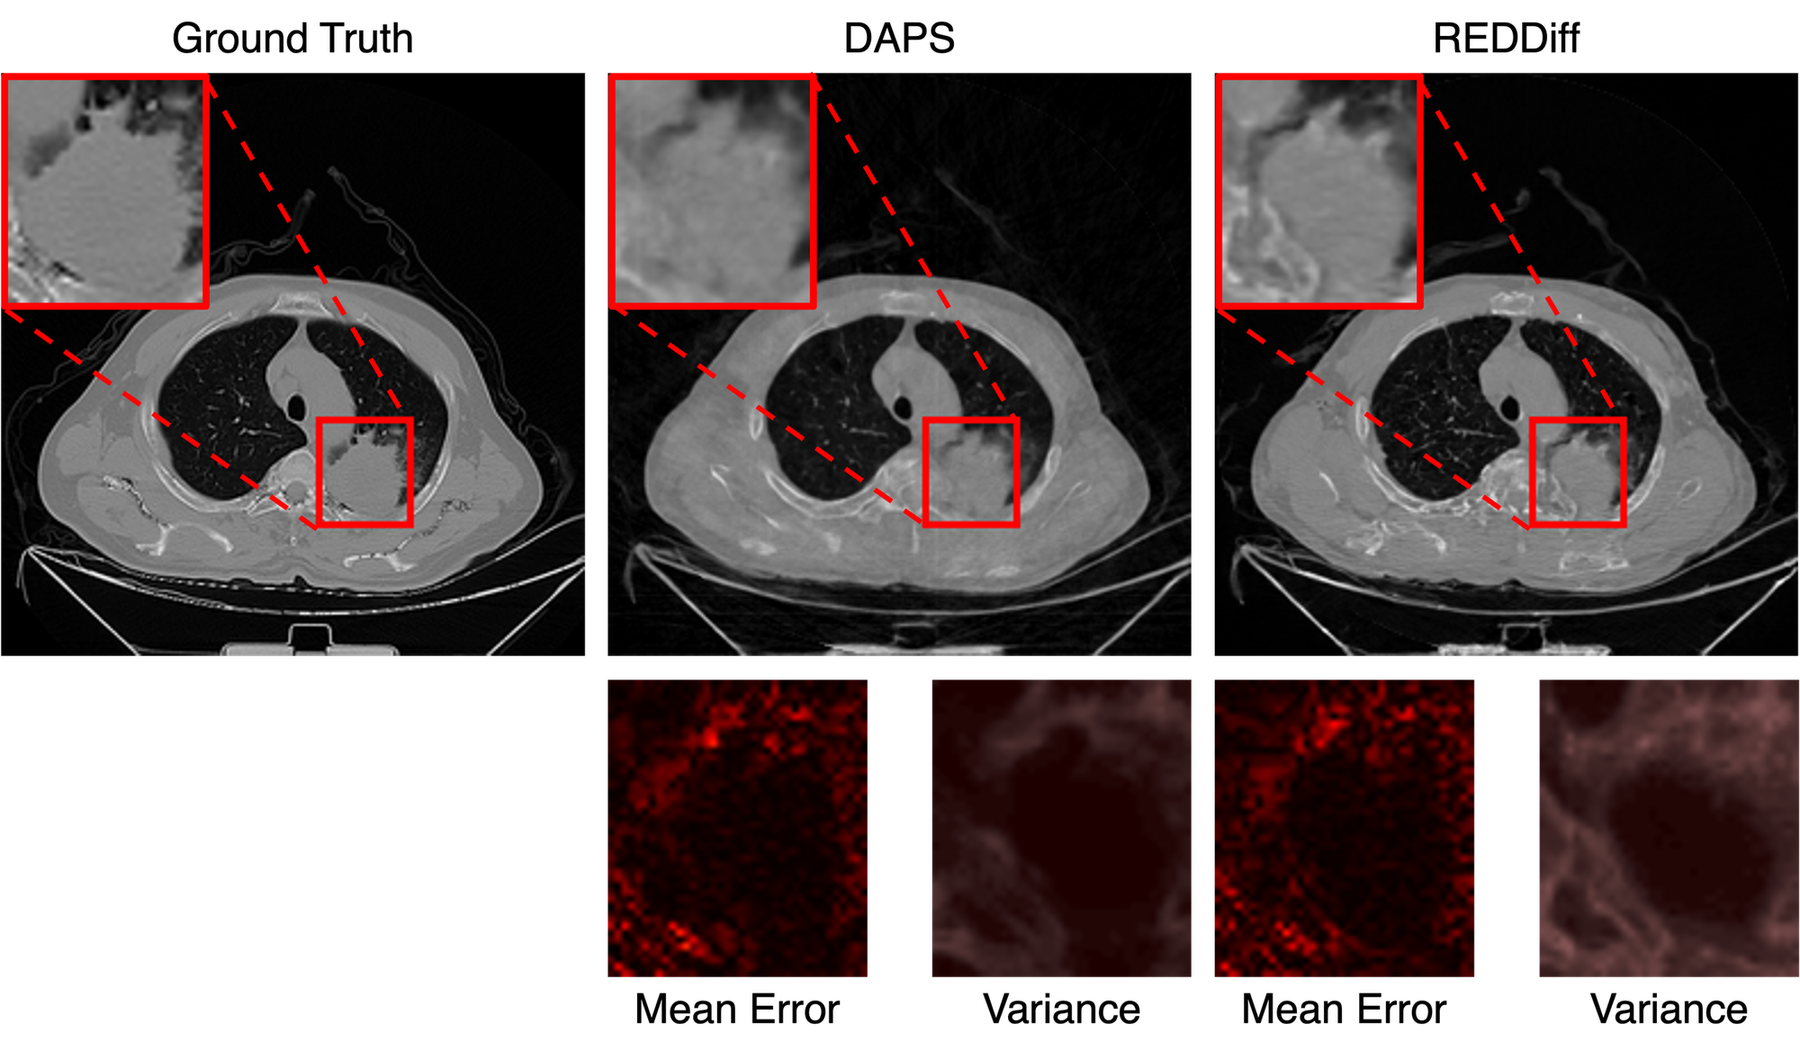

However, another gap on the evaluation objective remains. Natural image restoration tasks often reward pixel-wise accuracy (e.g., Peak Signal-to-Noise Ratio (PSNR)) from a random reconstruction (Kadkhodaie and Simoncelli, 2021), whereas scientific applications require distributional correctness on the unobserved posterior, i.e., calibrated uncertainty that preserves all physically valid solutions and enables principled risk quantification. This creates a potential misalignment: not only are we ignoring the inherent stochastic nature of diffusion generative solvers which can lead to multiple plausible reconstruction (Fig. 1), but we are also overlooking the critical role of uncertainty in scientific applications. This mismatch is evident in Fig. 2, where several PnPDP solvers produce similarly high-quality reconstructions under the same measurement, yet induce markedly different pixel-wise variance patterns across repeated runs.

Refer to caption

Figure 2: Similar reconstruction with distinct uncertainty. Comparison of PnPDP solvers on linear inverse scattering reconstruction with K=100K=100 times reconstruction on each solver. Top two Row: These methods produce similar reconstruction quality (in PSNR). Bottom Row: The pixel-wise variance maps reveal a fundamental difference. REDDiff(Mardani et al., 2023a) exhibits the lowest variance, while DPS(Chung et al., 2022) shows the highest uncertainty in structure-rich areas.

Most PnPDP solvers are inherently stochastic, generating samples by injecting randomness through diffusion models so the output under a fixed measurement yy is naturally a random variable XyX\mid y. Therefore, point metrics alone are insufficient to distinguish whether a solver is reliable or not. As demonstrated in Fig. 2, several solvers can yield similar reconstruction accuracy from a single sample, yet induce greatly different uncertainty. Existing evaluation benchmarks ignore this discrepancy, treating an overconfident solver and a calibrated solver as equivalent.